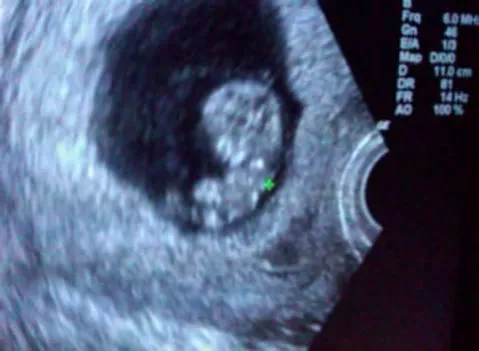

Ultrasound